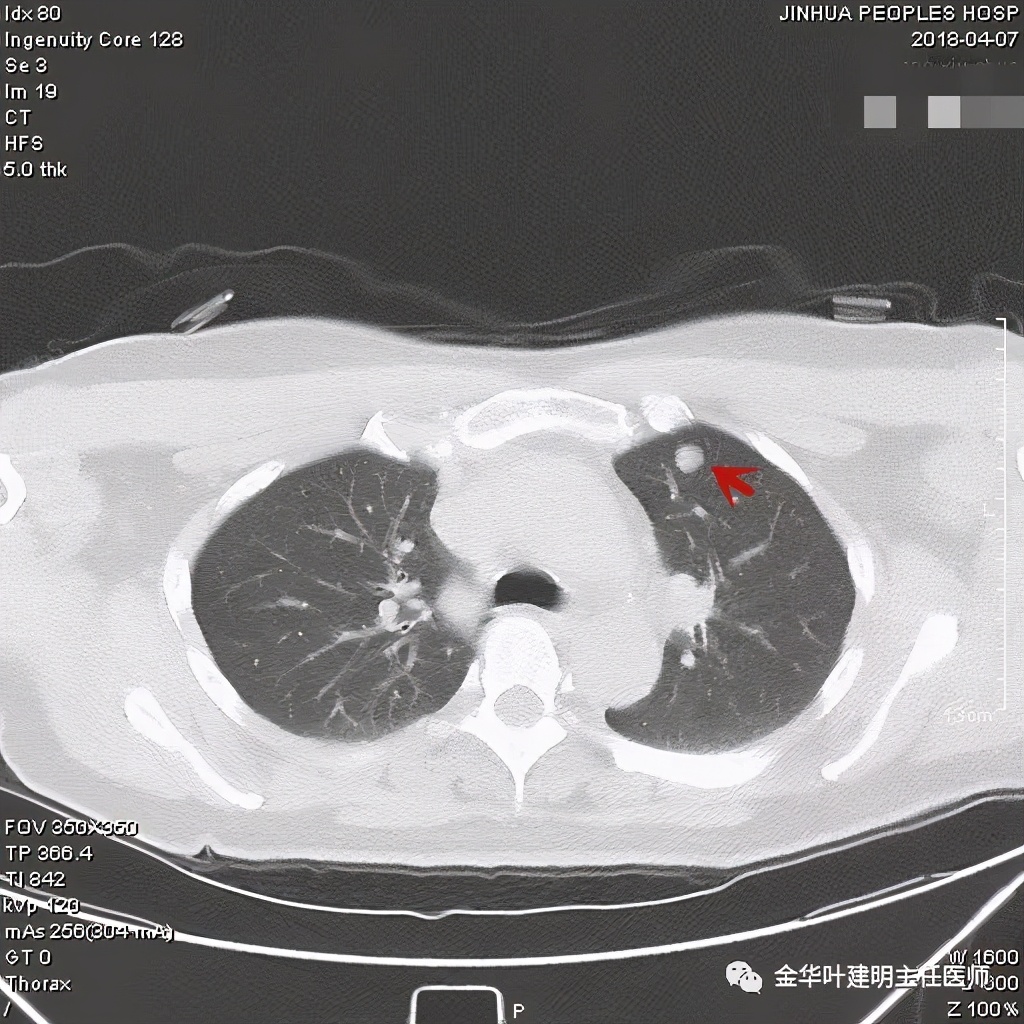

其实今天分享这个病例与我们以往的错构瘤不太一样,以前的影像如下:

亚厘米大小,密度高,周围型,血管贴边

密度高,周围部位,缺乏膨胀性,无收缩力

密度略不均,但边界甚清,边光峭

周围,边缘非常清,病灶内部有点状高密度,约1厘米许,似有微血管征